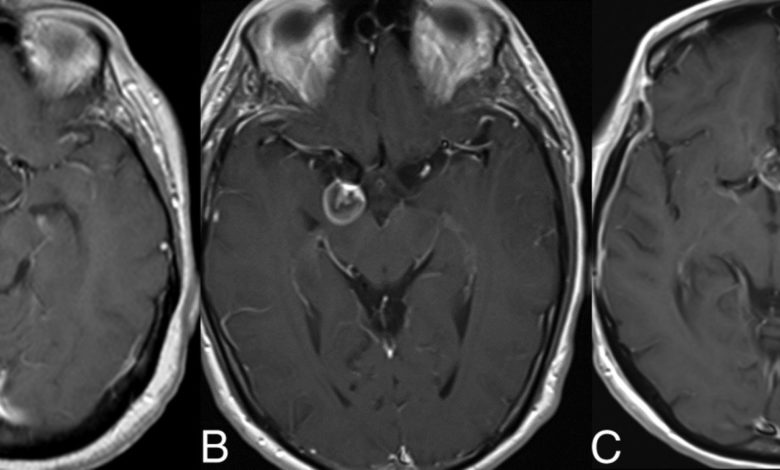

Dural arteriovenöz fistüller (Dural AVF’ler), beyni saran ve dura denen tabaka yüzeyindeki arterler (atardamar) ile venler (toplar damar) arasındaki anormal bağlantılardır (fistüller). Yer yer yumak tarzında düzensiz anormal damarlar eşlik eder. Dural arteriovenöz malformasyon olarak da isimledirilirler.

Tedavi seçenekleri içinde herhangi bir tedavi yapılmaması, konservatif yaklaşım, palyatif (kısmi ve şikayetlere yönelik) veya tam endovasküler (damar yoluyla) tedavi, cerrahi, endovasküler, cerrahi ve radyoterapi kombinasyon sayılabilir. DAVF’lerin doğal gidişi kendiliğinden tamamen gerilemesinden ölüme yol açan kanamalara kadar değişen geniş bir spektrum gösterir. Bu nedenle prognoz ve tedavi açısından tam bir anjiografik değerlendirme gerekir. Hangi tip olursa olsun, eğer intrakranyal basınç artışı var ise kesin tedavi gerekir.